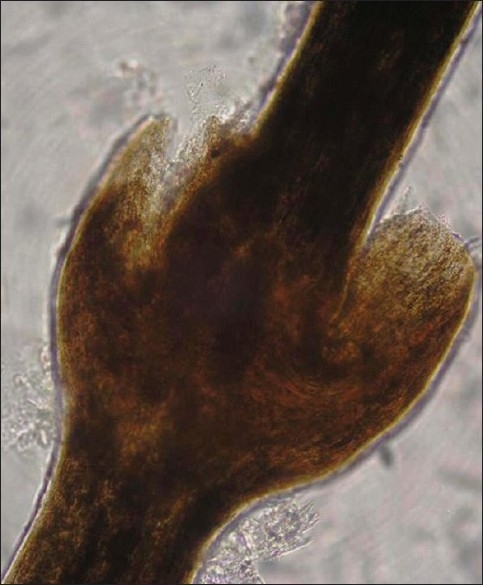

一名 24 岁的男性患者自出生以来就出现全身鳞状病变。 从小就存在皮损频繁加重和有效缓解的病史。 以反复性过敏性鼻炎为形式的特应性个人病史从孩提时代就存在。 无父母近亲史。 没有充满液体的病变史。 在一般检查中,患者适度构建和营养。 皮肤检查显示,皮损周围有多个广泛分布的环状多环状鳞状红斑,双刃鳞屑,累及躯干和四肢。 皮肤损伤在每次恶化期间不断改变其形状和大小,并且在愈合时不会留下疤痕或色素变化。 指甲有光泽。 头皮毛发稀疏、粗糙、无光泽。 黏膜等全身检查均在正常范围内。 血液检查显示血红蛋白 - 9.5 gm,白细胞计数 - 7300 个细胞/立方米,轻度嗜酸性粒细胞增多,红细胞沉降率升高 - 54 mm / h,血清 IgE 水平升高 - 11412.30 IU / ml。 头皮毛发的光学显微镜检查显示典型的毛发内陷(竹毛),毛干的远端部分内陷到近端部分。 背部病变的活组织检查与线状鱼鳞病的临床诊断一致。

图4:头皮毛发的光镜检查显示典型的内陷性毛发脱落(竹节状毛发)